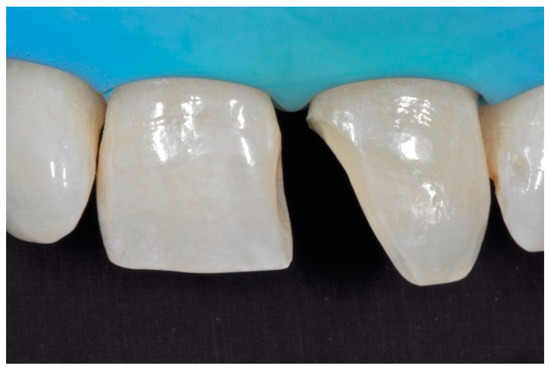

A healthy 38-year-old man referred to the dental office for the esthetic rehabilitation of left central maxillary incisor (Figure 41). Shade was selected as described in previous cases, using the button-try technique [14]. Isolation, preparation (Figure 42) and adhesive procedures were performed (Tokuyama Bond Force, Tokuyama Dental, Osaka, Japan). and Class III was restored on right central incisor (Asteria, A2B, Tokuyama Dental, Osaka, Japan). Frame was then completed on #2.1 (Figure 43) with the use of posterior sectional matrices using translucent and body material (Asteria, NE, A2B Tokuyama Dental, Osaka, Japan). After removing excesses both from the incisal margin and from the interproximal portion (Figure 44) silane and adhesive was applied strictly following the procedure described in Section 2.1.2. Dentinal body (Asteria, A2B, Tokuyama Dental, Osaka, Japan) was applied to reproduce internal anatomy (Figure 45) and then the external translucent enamel (Figure 46) (Asteria, NE, Tokuyama Dental, Osaka, Japan) was applied. The restoration shows good integration 6-months post-operative (Figure 47).

The frame completed.

Figure 44.

The frame modified either in the incisal frame and in the interproximal wall.